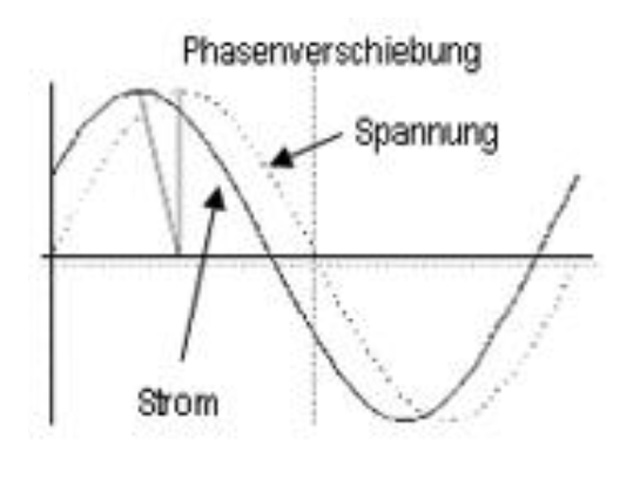

Exkurs: Phasen sensitive BIA

Bei Wechselstrom kommt es zu einer Verschiebung der Phase zwischen Strom und Spannung, dem sog. Phasenwinkel, der Strom läuft der Spannung hinterher.

Der Phasenwinkel im menschlichen Körper ist abhängig von der Masse, Integrität und Hydratation der Fettfreien Masse und wird häufig als Indikator für den Zustand der Zellmasse herangezogen.

Der Phasenwinkel verringert sich häufig beim Abbau von Zellmasse und kann somit zur Bestimmung des Ernährungszustandes herangezogen werden.

abnehmende Phasenwinkel können durch eine zunehmende extrazelluläre Wassermenge (ECW) verursacht werden. Die häufigsten Ursachen sind: – Muskelabbau (Kachexie) oder Überwässerung des Extrazellulärraumes als Folge einer Störung des Wasserhaushaltes (z. B. Niereninsuffizienz).

steigende Phasenwinkel können durch Dehydratation und/oder Aufbau von Zellmasse erklärt werden.

Die Kenntnis des Phasenwinkels kann zur allgemeinen Bewertung der „Gesundheit“ von Zellen benutzt werden, den Zellen ohne Defekte mit hoher Reaktanz = hohem kapazitivem Zellwiderstand bedeutet, dass die Zellmembran dicht und in Ordnung ist.